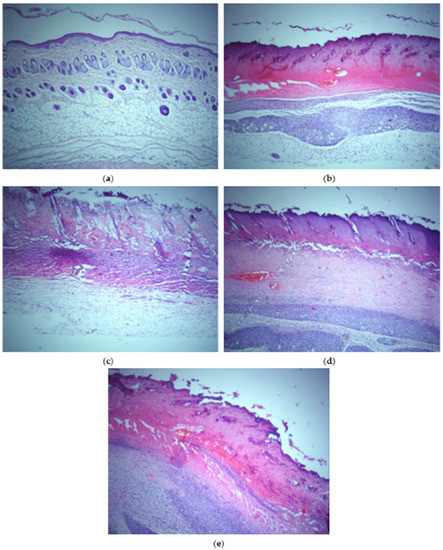

3.6. Cell Viability Assay and In Vivo Wound Healing Study